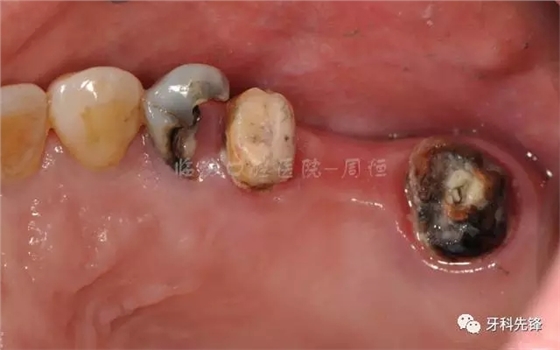

圖9去除腐質(zhì)口內(nèi)照

640.webp (13).jpg